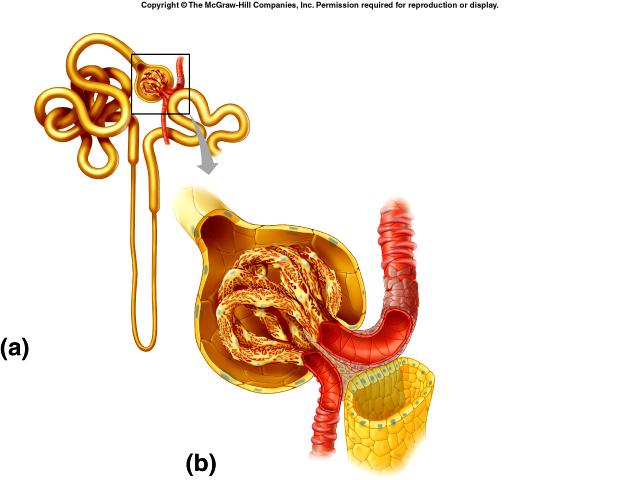

Collecting duct

Descending/Ascending loop (of nephron)

Distal (convoluted) tubule

Glomerular capsule (=Bowman's capsule)

Glomerulus (=glomerular capillaries)

Juxtaglomerular apparatus

Nephron

Peritubular capillaries

Proximal (convoluted) tubule

Renal corpuscle